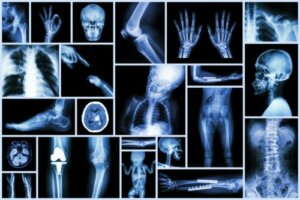

Like any other imaging study, X-rays allow us to learn about aspects of children’s bodies that we can’t see with the naked eye.

In the emergency room, a simple X-ray helps us to confirm the diagnosis of a fracture, detect the presence of a foreign body in the airway, or define if abdominal pain requires surgical treatment.

In other medical areas and disciplines, X-rays have brought endless benefits and we can be sure of that. In addition, they are quick, inexpensive studies, available in the vast majority of healthcare centers and that, in general, don’t require sedation or anesthesia procedures in order to be carried out.